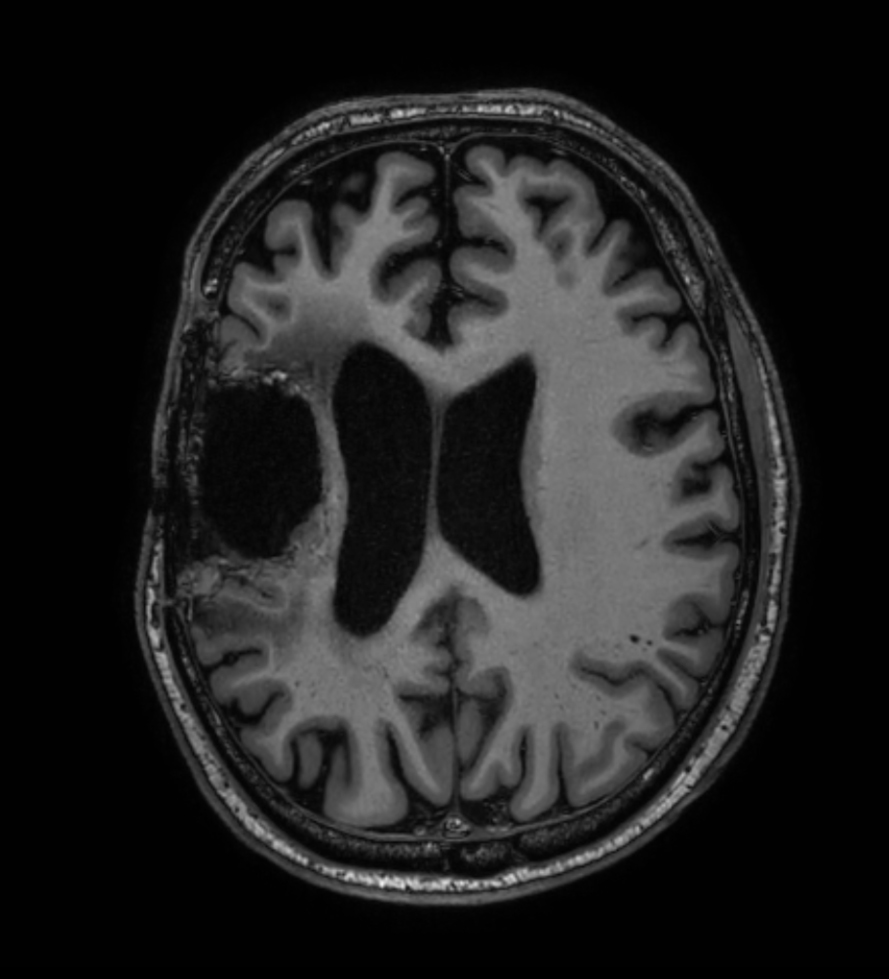

3D T1w TFE - Axial reformat (with gado)